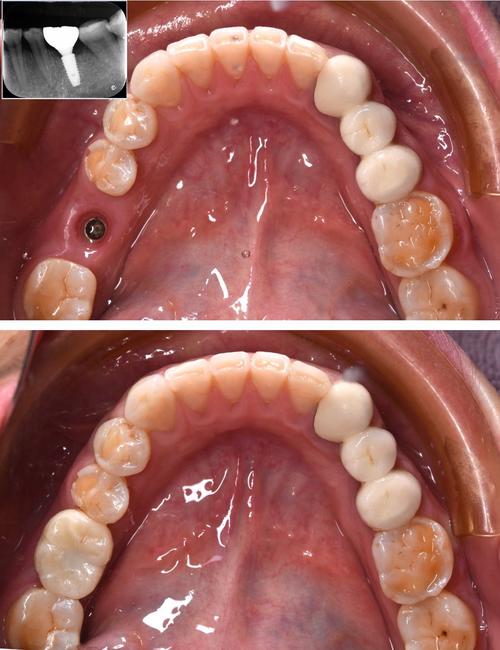

- 种植手术:

- 局部麻醉(。

- 消毒、铺巾。

- 切开牙龈、翻开黏骨膜瓣,暴露牙槽骨。

- 在牙槽骨上预备种植窝洞。

- 将种植体(人工牙根)植入预定位置。

- 可能同期进行植骨(如果骨量不足)。

- 缝合牙龈。

- 手术时间根据种植数量和复杂程度而定(单颗通常30-60分钟)。

- 数字化种植: 该医院广泛应用数字化技术,术前通过软件设计种植位置和角度,3D打印手术导板,术中导板引导种植体精准植入,提高安全性和成功率。

- 基台连接与取模:

- 骨结合完成后,进行二次小手术(或微创方式)暴露种植体顶部,连接愈合基台(引导牙龈成型)。

- 待牙龈形态稳定后,更换最终基台,并取模(或口内扫描)用于制作牙冠。

- 牙冠制作与佩戴:

- 技工所根据模型制作牙冠(烤瓷冠或全瓷冠)。

- 试戴牙冠,检查颜色、形态、咬合关系是否合适。

- 粘固牙冠,完成最终修复。